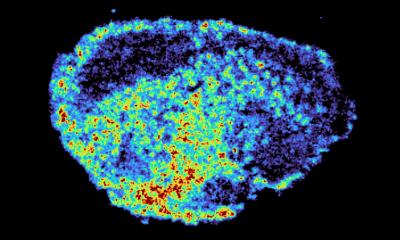

A novel subretinal implant shows promise could help patients with age-related macular degeneration (AMD) partially restore eyesight, a new study shows. Participants recovered their ability to read…